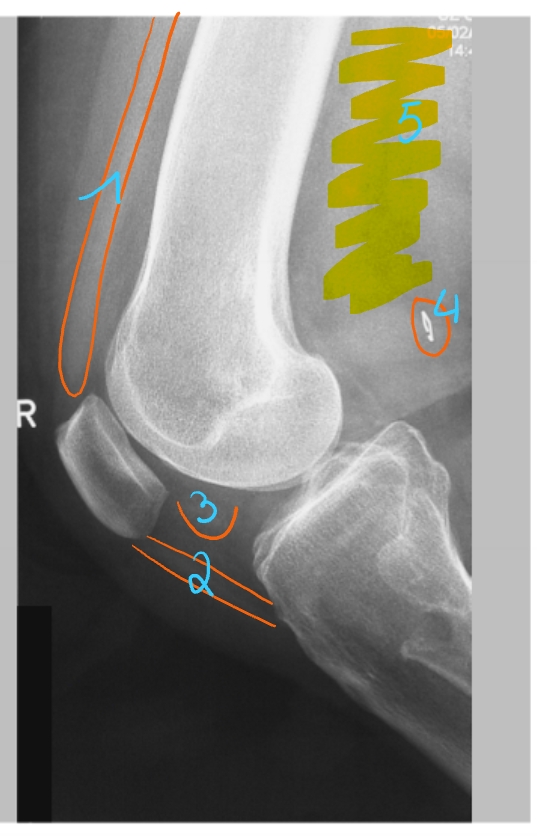

quadriceps-pees

redelijk dense structuur → absorbeert een beetje röntgenstralen (grijs)

patellapees = ligamentum patellae

vetweefsel

absorbeert niet veel röntgenstralen

stukje metaal

absorbeert veel röntgenstralen

patellaschijf

femurfractuur → intramedullaire nagel in het been (metaal)

pees van de m. quadriceps

basis patellae

facies articularis van de patella

apex patellae

patellapees/ ligamentum patellae

tuberositas tibiae

fibula

fabella = klein sesambeentje